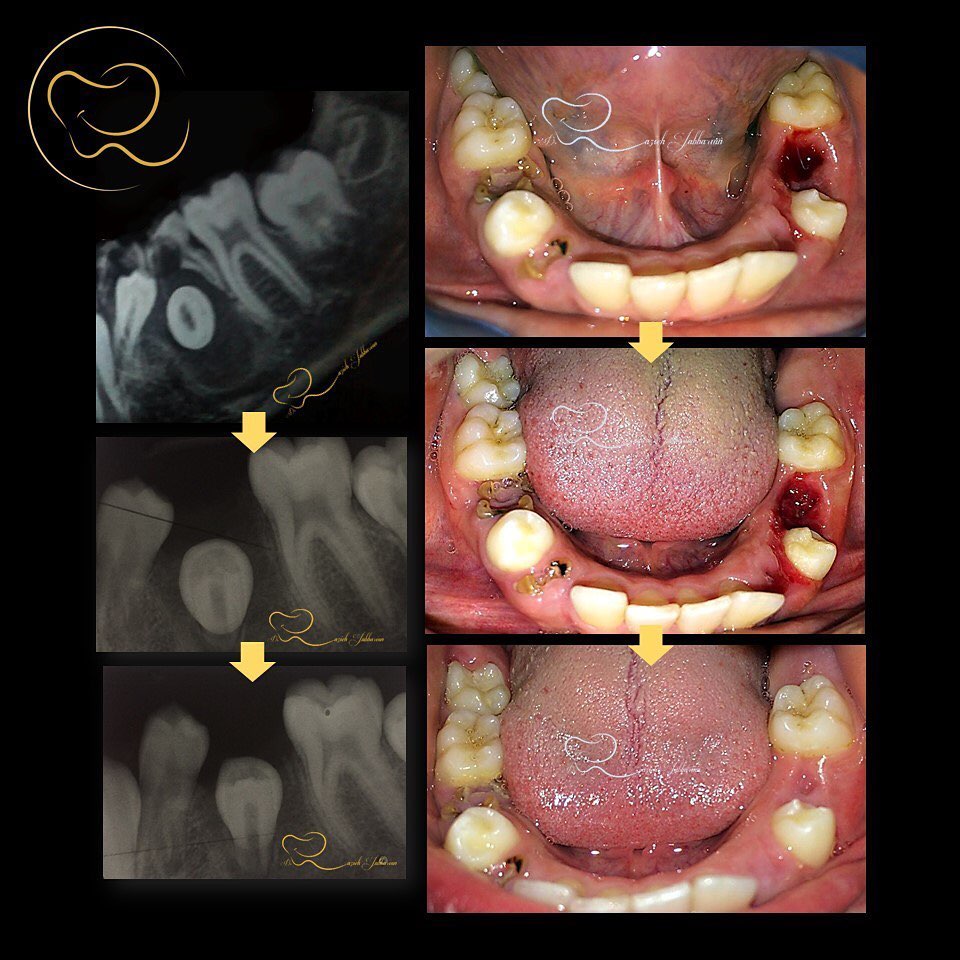

. دندان هاي شيري پوسيده كودك نياز به درمان دارند؛ در غير اينصورت، مخاطرات سيستم دنداني و سلامت كلي كودك اجتناب ناپذير است. يكي از مصاديق كودك آزاري، غفلت از سلامت دنداني كودك و عدم درمان دندان هاي پوسيده و علامت دار اين فرشته هاي معصوم است. . ساخت پلاك توسط جناب سعدي زاد توانا و هنرمند @dt.meysam.sadizad . . #كيست_دنداني #عفونت #سلامتي ‏#child_abuse #neglect #dentigetous_cyst